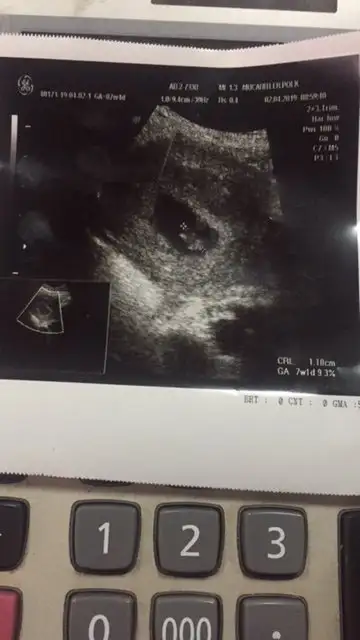

kızlar benim sat 21 şubat ilk 25 martta gittim kese 5mm di 31 martta 11,3 mm oldu sonra hafif kanama oldu 4 nisanda gittim dr kese aynı kalmış içi de boş dedi hemen araştırma hastanesine gittik keseyi 16mm ölçtü hatta bebek de var içinde dedi. bu cumartesi yani 6nisanda kese boş diyene gittik vajinalde 16mm kese 5.3 mm bebek gördü kalp atışı böyle beyaz ışık yanıp sönüyo gibiydi gösterdi ama kendi ile çelişmemek için mi nedir dinletmedi soru işareti koydu kalp atışı izlenmedi yazdı kağıda cumartesi bi daha çağırdı. ben de çarşamba yani 6+6 da devlete bi daha gidicem çok mu geç kalp atışı için :KK43: